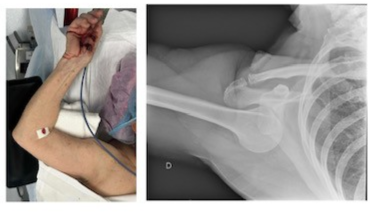

Une patiente de 79 ans est amenée par ambulance suite à une chute accidentelle vers l’avant avec réception à plat ventre sans souvenir exact de la position des bras. Elle ressent immédiatement une douleur au niveau de l’épaule droite avec une position vicieuse irréductible en abduction (photo 1).

La radiographie montre une luxation inférieure (sous glénoïdale) de l’épaule, sans fracture associée.